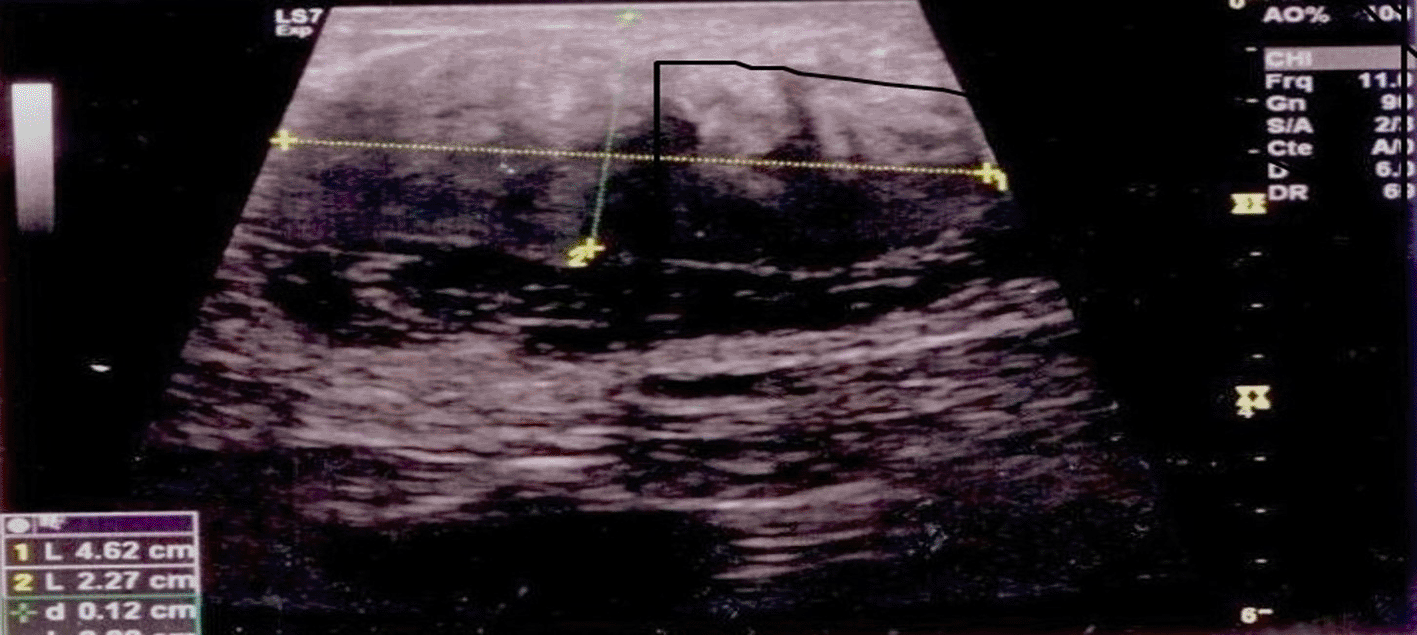

Breast ultrasound revealed a heterogeneous retroareolar hypoechoic formation on the right, measuring 5 × 3 cm, with irregular contours and attenuation of posterior echoes (Figure 1).

It revealed a right heterogeneous retroareolarhypoechoic, not well-limited formation of irregular contours of 5 × 3 cm in size with attenuation of the posterior echoes.

Ultrasound, on the other hand, is more concerning, as the lesion often appears as a hypoechoic formation with irregular contours and strong ultrasound attenuation, which are characteristics frequently observed in polymitotic processes.15 Among the signs suggestive of malignancy, posterior acoustic shadowing and indistinct margins.16 Ultrasonographic abnormalities were observed in our patient.